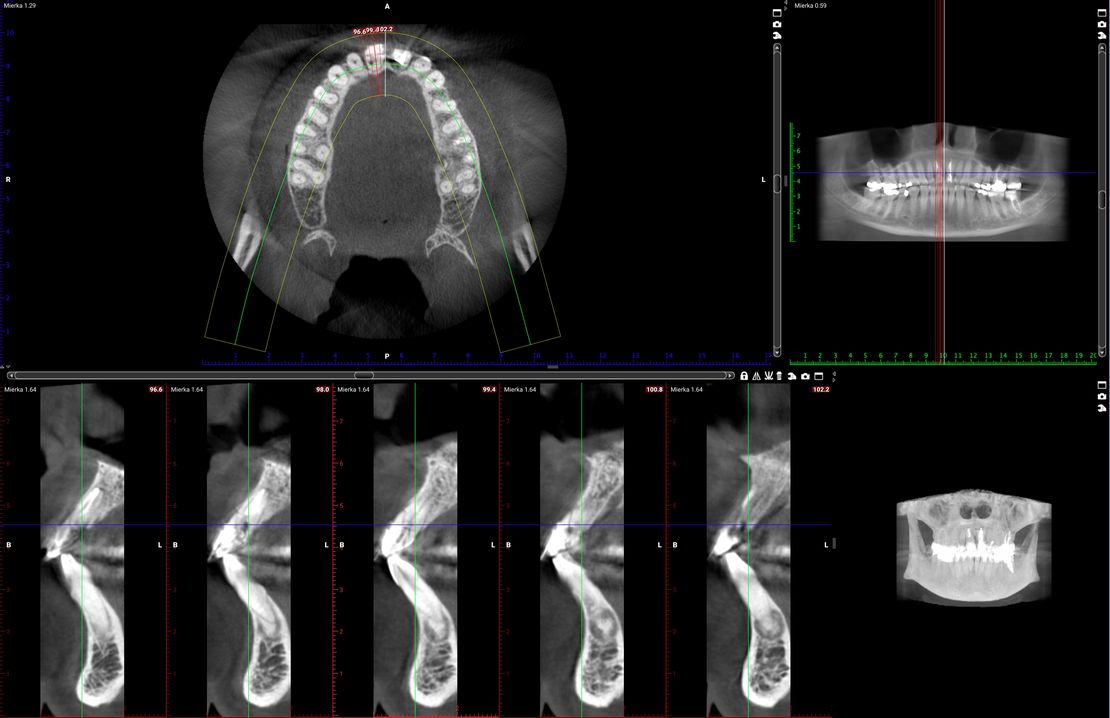

45-ročná pacientka sa obrátila na našu kliniku s bolesťou v oblasti horných stredných rezákov (obr. 1). Pri dôkladnom vyšetrení a CT diagnostike bola v oblasti zuba č. 11 zistená vertikálna fraktúra koreňa (obr. 2). V oblasti zuba č. 21 palatinálne bol prítomný hlboký kaz koreňa (obr. 3).

Jediným riešením bola extrakcia obidvoch zubov. Najväčšou obavou zo strany pacientky bola strata obidvoch predných zubov a následného fungovania bez nich pri práci s ľuďmi. Ideálnym riešením teda bola náhrada zubov implantátmi spolu s nasadením koruniek, a to počas jedného sedenia. V deň konzultácie bol pacientke urobený sken pomocou intraorálneho skeneru 3Shape TRIOS, ktorý nám umožňuje zobraziť 3D simuláciu ústnej dutiny. Pomocou softwaru 3Shape Implant Studio sme spojili dáta z intraorálneho skenu a CBCT, STL a DICOM súbory. V ďalšom kroku sme virtuálne vložili implantáty v správnej protetickej polohe, navrhli šablónu pre ich zavedenie, namodelovali individuálne abutmenty a korunky (obr. 4). Kompletné dáta sme exportovali pre frézovanie a 3D tlač. V laboratóriu sa pomocou 3D tlačiarne vytlačila chirurgická šablóna, ktorá nám slúži na presné zavedenie implantátov – použili sme implantačný systém Dentium Super Line. Následne boli vyfrézované zirkonové abutmenty a plastové dočasné korunky(obr. 5).